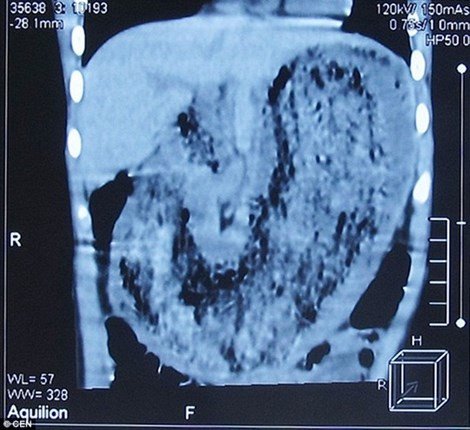

Một bé gái Liuniu Liang, 8 tuổi, ở Chu Khẩu, tỉnh Hà Nam, Trung Quốc được đưa tới bệnh viện sau khi có biểu hiện ói mửa, bỏ ăn, sụt cân. Lúc tiến hành kiểm tra cho Liuniu, các bác sĩ ngạc nhiên khi phát hiện ra nguyên nhân là do có một búi tóc 2kg mắc trong hệ tiêu hóa của cô bé, khiến em không thể ăn được gì. Bác sĩ Zhang Shufeng còn nhận thấy không chỉ ăn tóc, bé gái này còn thích nhai nuốt cả móng tay và quần áo.

Nghiện ăn tóc, thiếu nữ bị búi tóc 4kg đâm "thủng" dạ dày. Sau khi có những triệu chứng không thể ăn hay uống nước mặc dù không mắc bệnh gì trong thời gian gần đây, cô gái trẻ Ayperi Alekseeva, sống tại Kyrgyzstan, Nga mới bắt đầu tới bệnh viện để kiểm tra sức khỏe. Tại đây, các bác sĩ đã phát hiện ra một búi tóc lớn đang khóa chặt hệ tiêu hóa của cô lại.

Búi tóc mắc trong dạ dày của Ayperi nặng tới 4kg. Do các sợi tóc và lông thảm đâm vào thành dạ dày nên dạ dày của cô phù nề và rỉ ra nhiều dịch máu ngay khi dao mổ chạm vào.